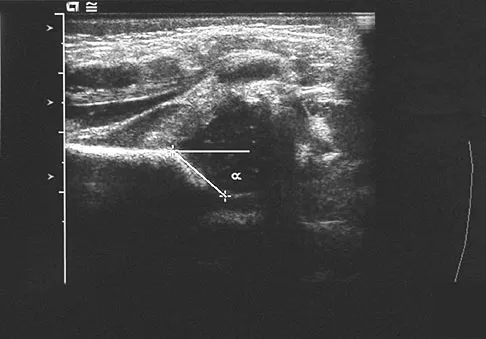

A 28-year-old professional dancer reports a 3-month history of progressive pain in the posterior aspect of the left ankle. Her symptoms are worse when she assumes the en pointe position. Examination reveals tenderness to palpation at the posterolateral aspect of the ankle posterior to the peroneal tendons which is made worse with passive plantar flexion. There is no nodularity, fluctuance, or tenderness of the Achilles tendon. The neurovascular examination is unremarkable. A lateral radiograph and MRI scan are shown in Figures 16a and 16b, respectively. Management should consist of

The imaging studies reveal findings typical of the os trigonum syndrome. This condition results from inflammation between the os trigonum and the adjacent talus. The symptoms of posterior ankle pain are exacerbated by plantar flexion, which stresses the fibrous union between these two bones. Definitive management of the high-level athlete involves excision of the os trigonum from a medial approach, although arthroscopic excision has also been described. The os trigonum is not an intra-articular structure; therefore, ankle arthroscopy is neither diagnostic nor therapeutic. Abramowitz Y, Wollstein R, Barzilay Y, et al: Outcome of resection of a symptomatic os trigonum. J Bone Joint Surg Am 2003;85:1051-1057. Mouhsine E, Crevoisier X, Leyvraz P, et al: Post-traumatic overload or acute syndrome of the os trigonum: A possible cause of posterior ankle impingement. Knee Surg Sports Traumatol Arthrosc 2004;12:250-253.